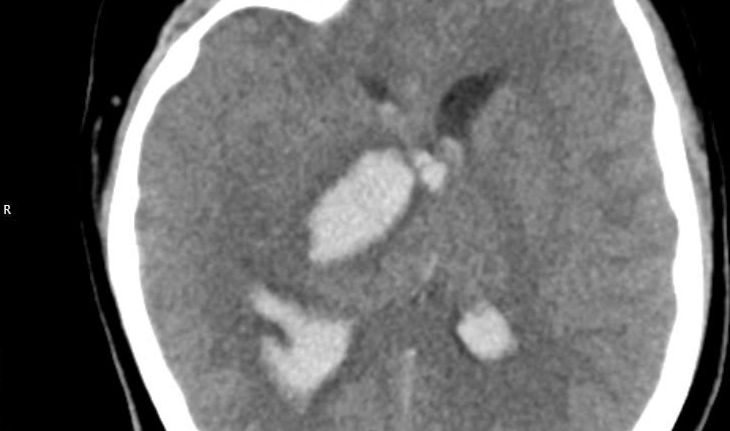

Hình ảnh chụp phim chảy máu não đồi thị của bệnh nhi 15 tuổi. (Ảnh: BVCC)

Trường hợp thứ nhất là bệnh nhân 15 tuổi, đến viện vì đột ngột đau đầu dữ dội. Bệnh nhi nhanh chóng rơi vào tình trạng hôn mê. Bệnh viện tuyến dưới tiếp nhận chẩn đoán, bệnh nhi bị chảy máu não. Tại đây, bệnh nhi được đặt ống nội khí quản thở máy và nhanh chóng chuyển ngay đến Bệnh viện Bạch Mai.

Mặc dù đã được hồi sức tích cực tại Trung tâm Đột Quỵ nhưng tình trạng diễn biến nhanh, bệnh nhân tụt huyết áp, thiểu niệu, rối loạn thân nhiệt, hôn mê sâu. Sau 2 ngày điều trị, khi được bác sĩ giải thích không còn khả năng cứu chữa, gia đình đưa bệnh nhi về. Bệnh nhi tử vong sau đó.